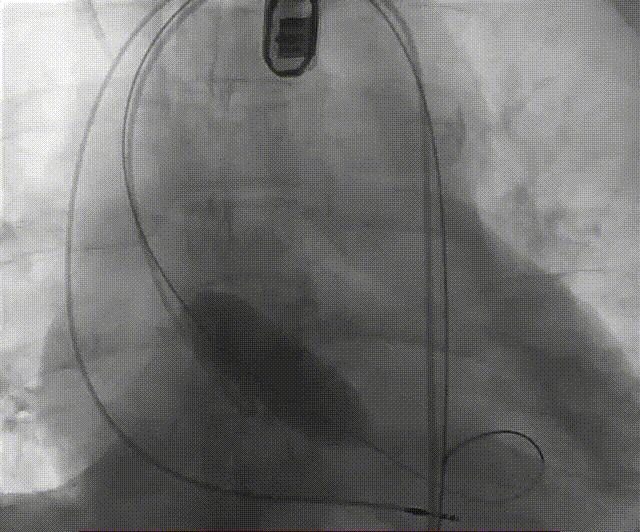

根部造影

左冠脉提前植入延长导管,预埋冠脉导丝。

20mm球囊预扩张,无腰征,无造影剂泄露。

vitaflow tav24瓣膜轻松过弓初始定位瓣环0位开始释放,班第一次释放瓣膜在转移到瓣上,综合决定回收采取第二次瓣膜释放。

第二次精准零位释放,决定完全释放。

释放后多体位观察造影,瓣膜位置良好,展开良好,轻微瓣周漏。